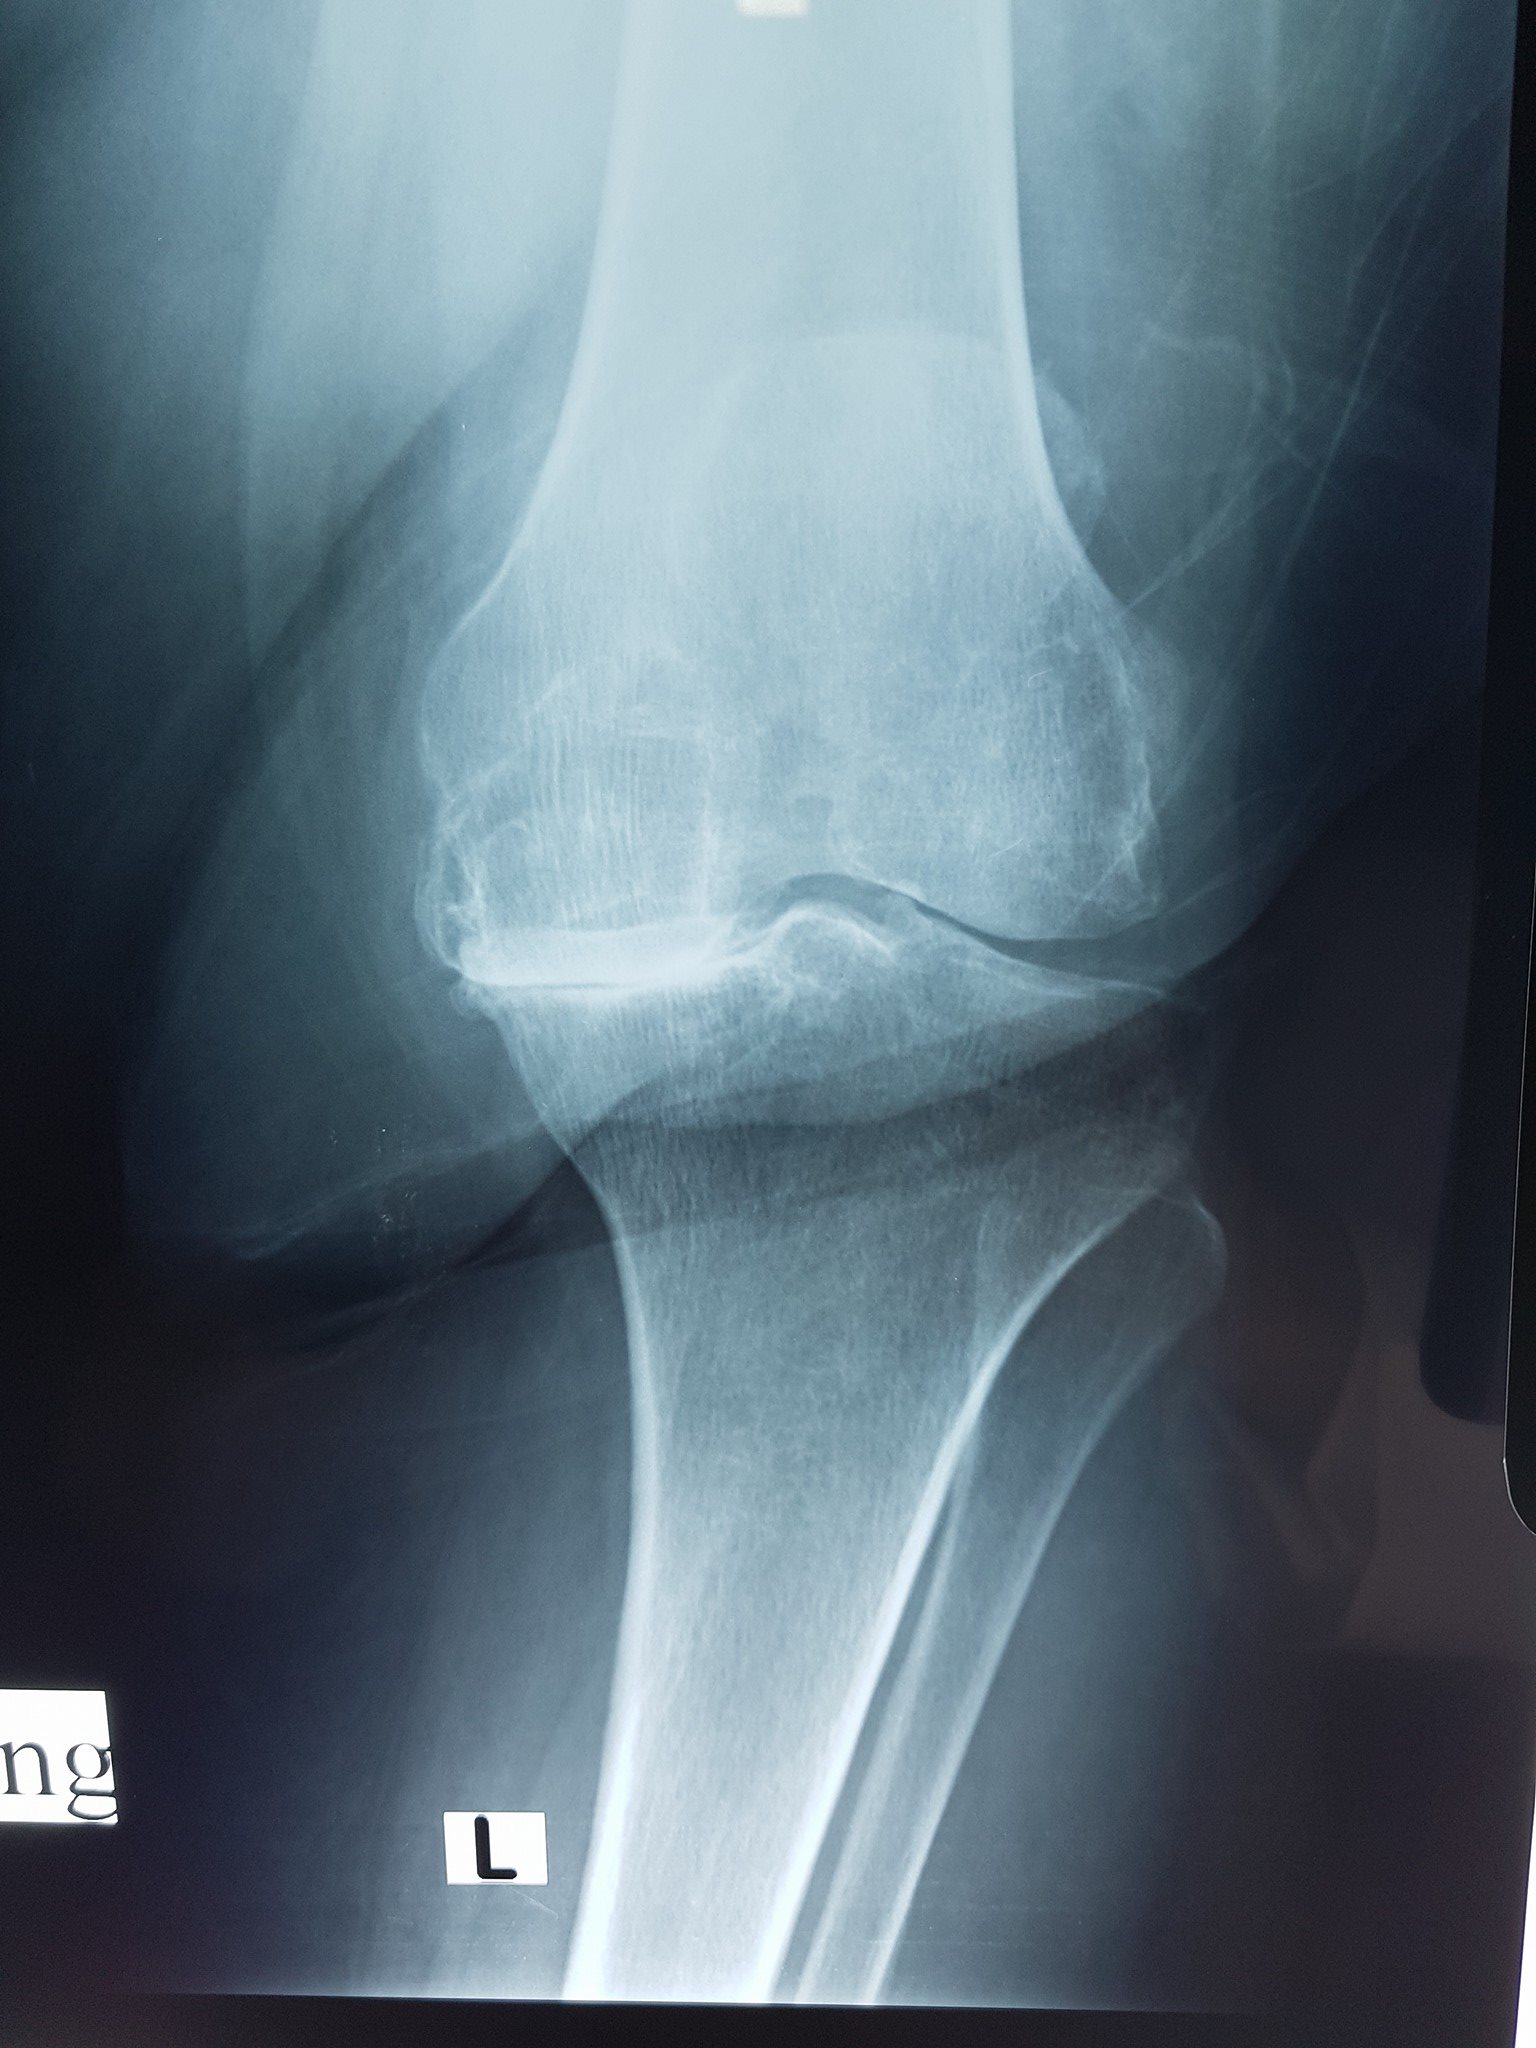

جراحة العظام والمفاصل

كافة انواع الكسور وعلاجها